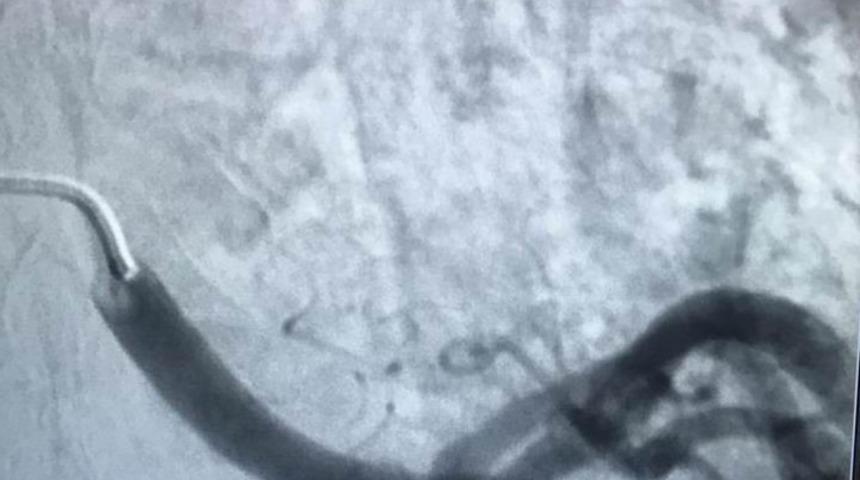

Kayseri Şehir Hastanesi’nde uygulanan periferik arterlerde anevriz tedavisi, hastaların iyileşmesinde etki gösteriyor. Karın ağrısı nedeniyle Kayseri Şehir Hastanesine başvuran hasta, yapılan tetkikler sonrası splenik arterinde halk arasında baloncuk olarak bilinen anevrizmatik genişleme olduğu saptandı. İleri tetkik ve tedavi için girişimsel radyoloji ünitesine yönlendirilen hastaya, periferik arterlerde anevriz tedavisi uygulandı.

Kayseri Şehir Hastanesi Girişimsel Radyoloji Uzmanı Doktor Mustafa Özdemir’in yaptığı tedavide, hastanın kasığından girilerek genişlemiş damar bölgesi içine ulaşıldı ve anevrizma kapatıldıç 1.5 saat süren işlem sonrasında hasta, 1 gün gözlem altında tutulduktan sonra taburcu edildi ve normal hayatına döndü.